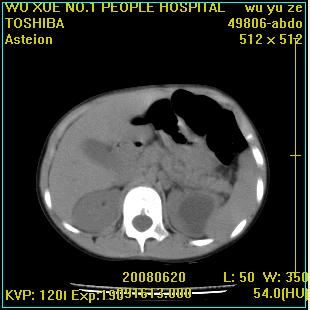

标题: PED0851:患儿,7岁,左腰部外伤一天,伴大量肉眼血尿。 [打印本页]

标题: PED0851:患儿,7岁,左腰部外伤一天,伴大量肉眼血尿。

左甚积液,输尿管近端扩张,考虑输尿管中下段梗阻

左侧输尿管中段狭窄伴输尿管肾积水,考虑先天性狭窄可能性大.

左肾重度积水,原因不明;不排除左输尿管上段迷走血压迫或先天性狭窄所致可能。

左肾重度积水

支持左肾积水,输尿管上段扩张.考虑左输尿管下段狭窄受阻。

左输尿管上段梗阻伴左肾盂肾盏扩张积液

支持!建议增强进一步检查。